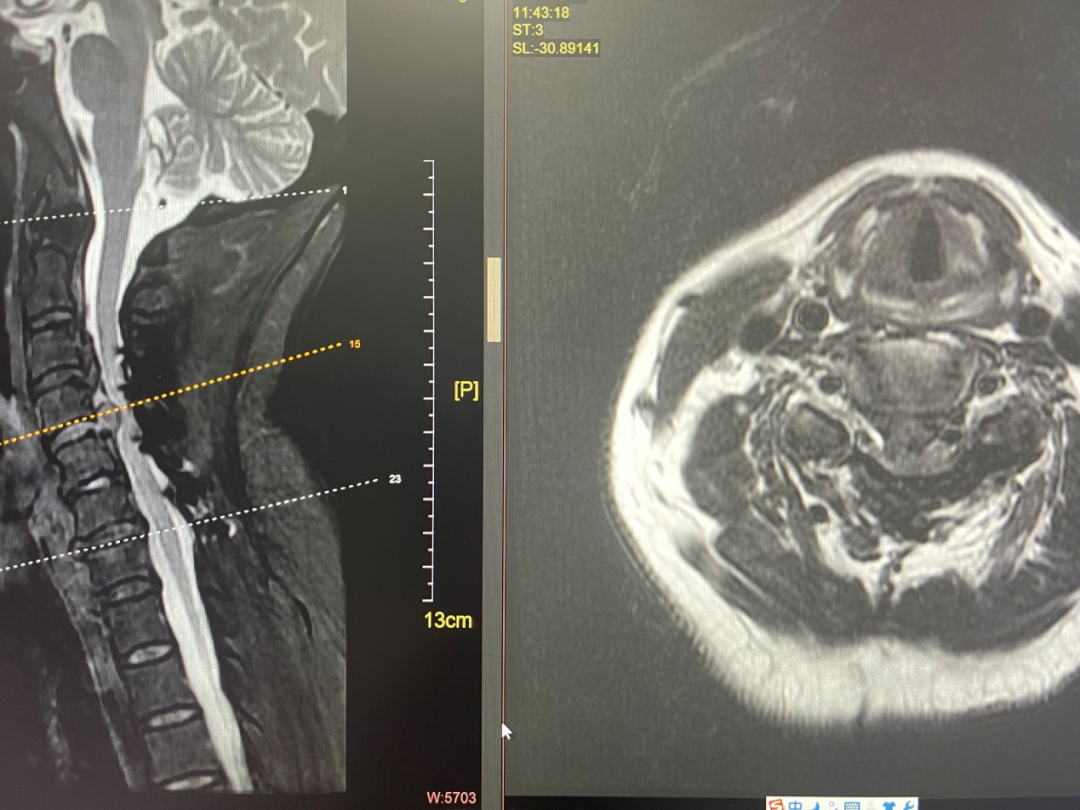

赵斌修阅片发现吴女士的颈4/5椎间盘呈巨大的脱出状、占据椎管前后径的75%以上。“脱出的椎间盘紧邻颈部脊髓并造成压迫,在颈髓已经受到严重压迫的状态下,术者在手术中稍有不慎失手即可对颈髓造成不可回逆的毁灭性损害。”手术一旦失败,直接后果就是“高位截瘫”——吴姨需要面临后半辈子将要在轮椅上度过的困难境遇。

▲患者术前MRI